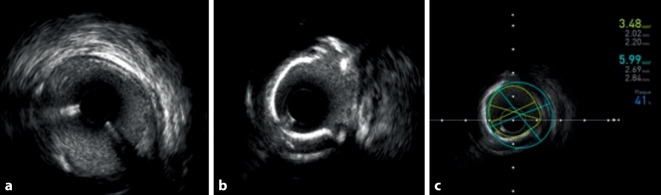

This section collects any data citations, data availability statements, or supplementary materials included in this article.